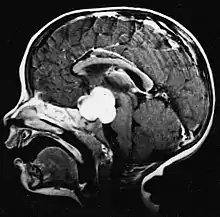

Pilocytic astrocytomas are often cystic tumors, and, if solid, tend to be well-circumscribed.

Usually – depending on the interview of the patient and after a clinical exam which includes a neurological exam and an ophthalmological exam – a CT scan and/or an MRI scan will be performed to confirm the presence of a tumor. They are usually easily distinguishable from normal brain structures using these imaging techniques. A special dye may be injected into a vein before these scans to provide contrast and make tumors easier to identify. Pilocytic astrocytomas are typically clearly visible on such scans, but it is often difficult to say based on imaging alone what type of tumor is present.